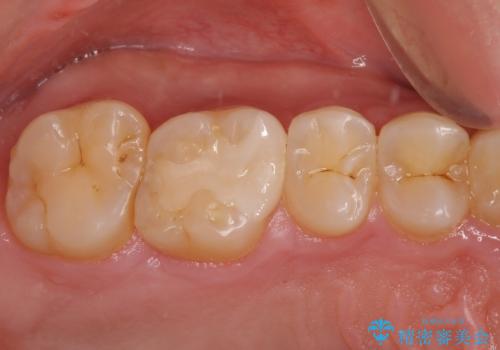

根管治療のやり直しは希望されなかったため、土台のやり替えと、より自然なオールセラミッククラウンへのやり替えを行いました。

自然できれなオールセラミッククラウンになり、とても満足されました。